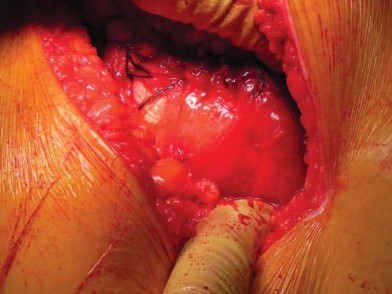

إدارة الأنسجة الرخوة وخلع رأس الفخذ

تُشق اللفافة العريضة والألياف الأمامية للعضلة الألوية الكبرى التي تتصل باللفافة العريضة قريبًا باستخدام الكي الكهربائي بما يتماشى مع شق الجلد. يتم إزاحة الجراب المدوري خلفيًا للمساعدة في رؤية العضلة الألوية الوسطى والعضلة المتسعة الجانبية. يتم رفع الجزء الأمامي من العضلة الألوية الوسطى عن المدور الكبير باستخدام الكي الكهربائي، ثم يتم تشريحه بشكل غير حاد بما يتماشى مع أليافه بزاوية 45 درجة أمامية-قريبة عند تقاطع الثلثين الأوسط والأمامي للعضلة. يقتصر التشريح على أقل من 3-4 سم باتجاه الرأس من طرف المدور الكبير لتجنب إصابة العصب الألوي العلوي. في غلاف مستمر مع العضلة الألوية الوسطى، يتم رفع الجزء الأمامي من العضلة المتسعة الجانبية عن حافة العضلة المتسعة ويتم شقه بعيدًا بين ثلثيه الأوسط والأمامي. يتم وضع مبعد هومان غير حاد في شق العضلة الألوية الوسطى لسحب الألياف الخلفية وكشف طبقة من الدهون بين المستويات الألوية. تُشق الكبسولة خلف العضلة الألوية الصغرى وعلى طول الجانب العلوي من عنق الفخذ. يقوم المساعد بتباعد وثني وتدوير الطرف خارجيًا لخلع رأس الفخذ.